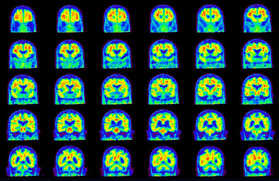

Head / Case5 : Amyloid

Coronal

Courtesy : Kindai University Hospital

- Imaging protocol

- Injected dose: 4.27 MBq/kg, 18F-Flutemetamol

- Uptake time: 99 minutes

- Scan time: 20 minutes